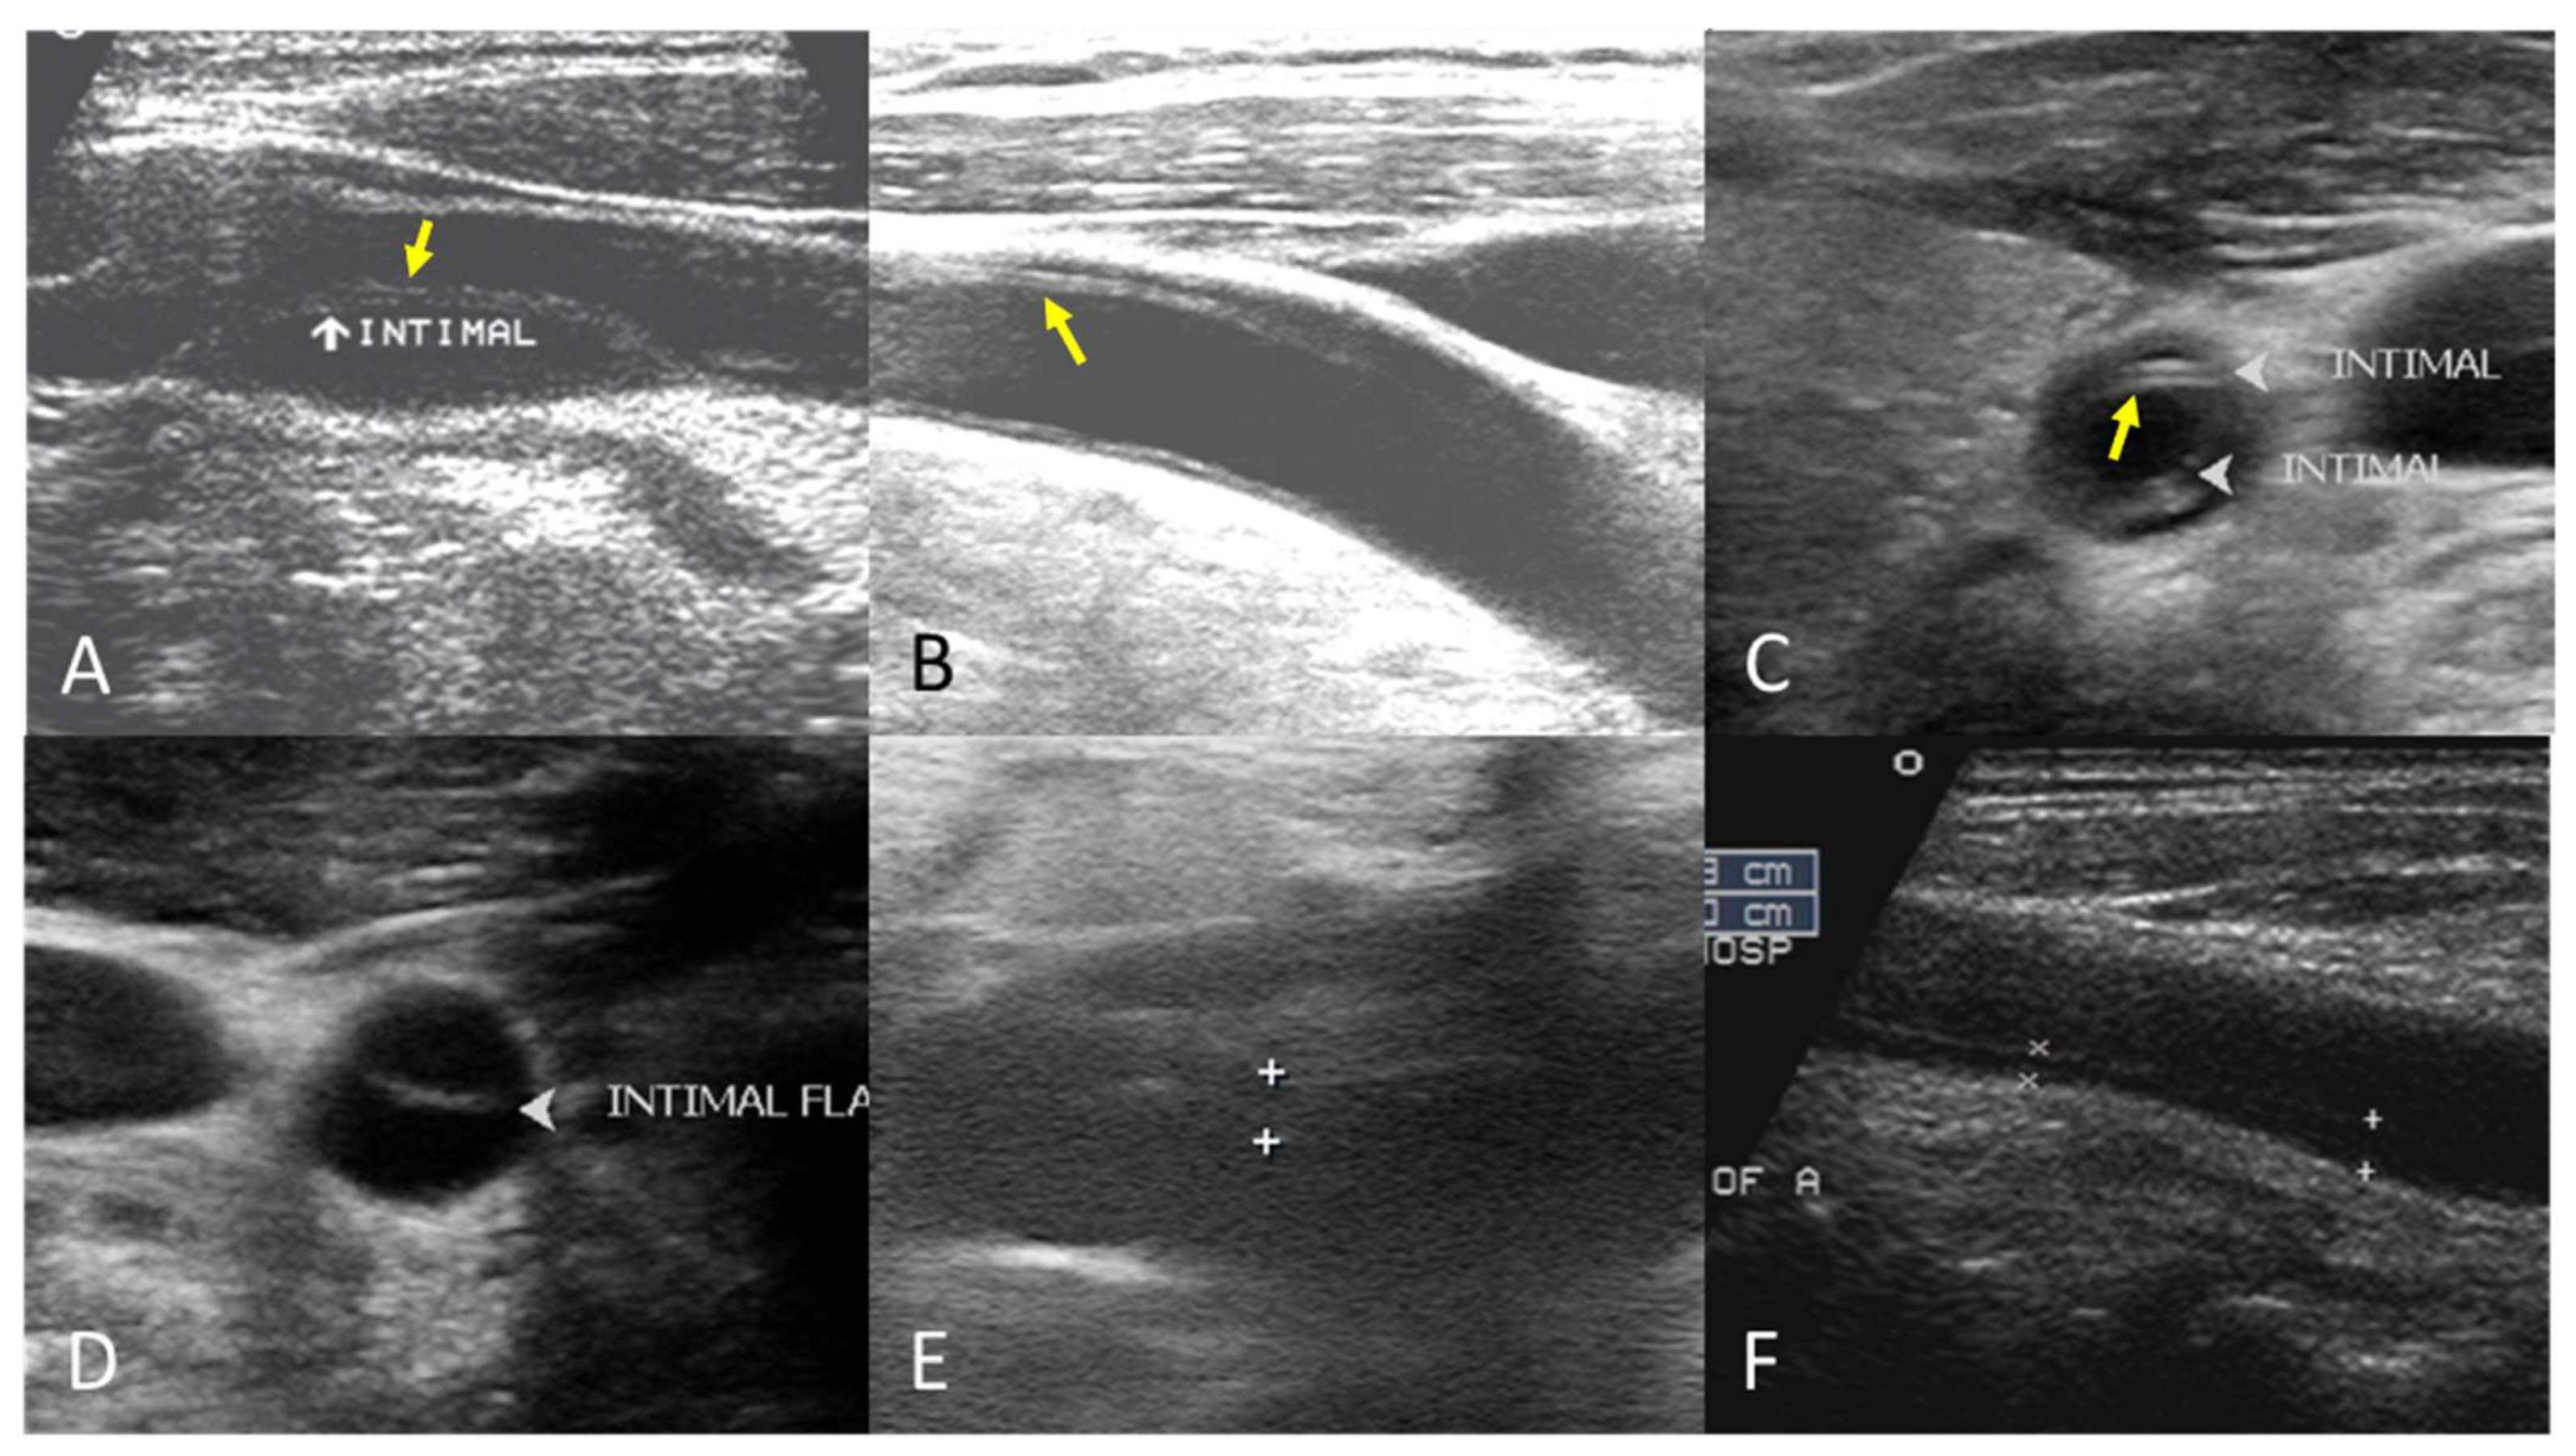

The B-mode findings of the nine CCAs revealed six typical double lumens with intimal flaps (Figure 2) and three intramural thrombi, which are also termed thrombosed false lumen (Figure 3). Supplementary Figures S1 and S2 contain the original ultrasound images. The “train-line” pattern was recognized in three of six intimal flaps and two of three intramural thrombi. The extracranial duplex sonography revealed a “train-line” pattern characterized by a thickened wall displaying hypoechoic properties, where the boundary was composed of closely placed parallel linear reflections. Patient No. 1 corresponds to Figure 2A; patient No. 2 corresponds to Figure 2B; patient No. 3 corresponds to Figure 2C,D; patient No. 4 corresponds to Figure 2E; and patient No. 5 corresponds to Figure 2F. Patient No. 6 corresponds to Figure 3A; patient No. 7 corresponds to Figure 3B; and patient No. 8 corresponds to Figure 3C. Interestingly, patient No. 5 had bilateral CCAD, but the train-line pattern was only on the right side. Figure 2C shows the right CCA with a double lumen and a clearly visible train-line pattern, and Figure 2D displays the left CCA, which also demonstrates a double lumen, but no train-line pattern is observed. Patient No. 8 presented with a hypoechoic intramural thrombus which resembled double lumens, but it was easy to distinguish under the color Doppler imaging.

Figure 2.

Double lumen with intimal flap with train-line pattern (A–C) and without train-line pattern (D–F). The ultrasound image was obtained using a 4× magnification setting. Yellow arrows indicate the “train line”. The train-line pattern is characterized by two closely positioned, hyperechoic parallel linear reflections overlying a thickened vessel wall. Symbols such as “×”, “+”, arrows, and arrowheads were generated by the ultrasound machine and used by sonographers to mark regions of interest (ROIs) where the intimal flap was located.

The following supporting information can be downloaded at https://www.mdpi.com/article/10.3390/diagnostics15101297/s1, Figure S1: Original B-mode ultrasound images of CCAD patients with double lumen and intimal flap with train-line pattern (A–C) and without train-line pattern (D–F); Figure S2: Original B-mode ultrasound images of CCAD patients with intramural thrombus with train-line pattern (A,B) or without train-line pattern (C). Table S1: Doppler waveforms of patients No. 1 to No. 8.